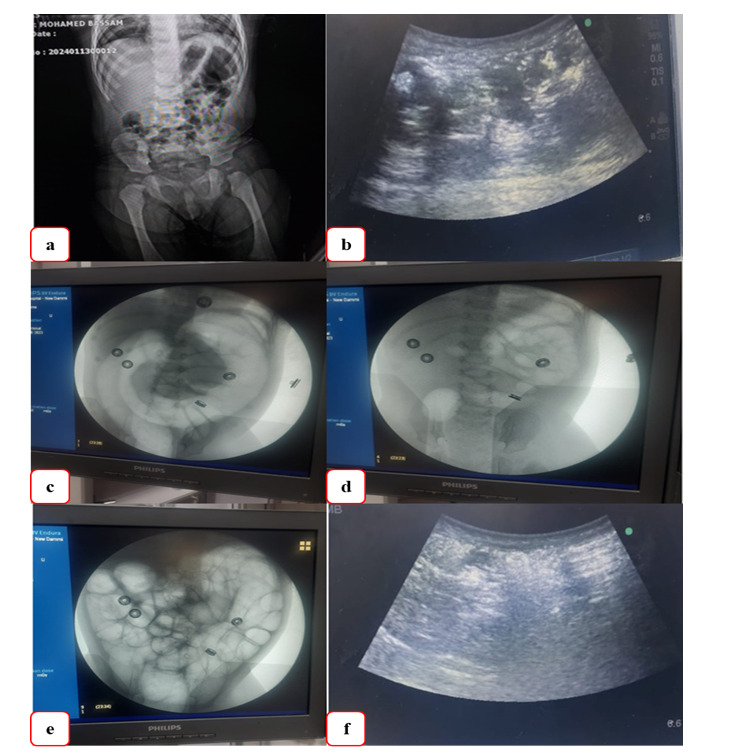

Methods: This prospective study was done throughout the time between January 2023 and January 2024 by collaboration between the Pediatric Surgery Unit and Diagnostic Radiology Departments, Al-Azhar University Hospital, New Damietta, Egypt. Under general anesthesia, pneumatic reduction guided by fluoroscopy was performed on all intussusception patients. Children with pathologic lead points discovered by ultrasonography, those with symptoms of intestinal perforation or peritonitis, and those who were hemodynamically unstable were excluded. Statistical analysis of the obtained data was done using the SPSS program (version 20).

Results: In all, 34 children between the ages of 3-28 months, pneumatic reduction under general anesthesia was successful in 32 individuals (94.1% overall). On the first trial, the intussusception was succeeded in 26 patients; on the second try, it was reduced in 5 patients, and in the third, in 1 patient. In two cases, the intussusception failed after three successive trials. One of them was diagnosed as an extended intussusception mass, which was later surgically confirmed, and the other was an appendico-cecal intussusception. During the reduction efforts, there was no bowel perforation or death reported.

Conclusion: As a first-line therapy for pediatric intussusception, fluoroscopy-guided PR under GA is straightforward, risk-free, and successful, with no complications or mortalities.